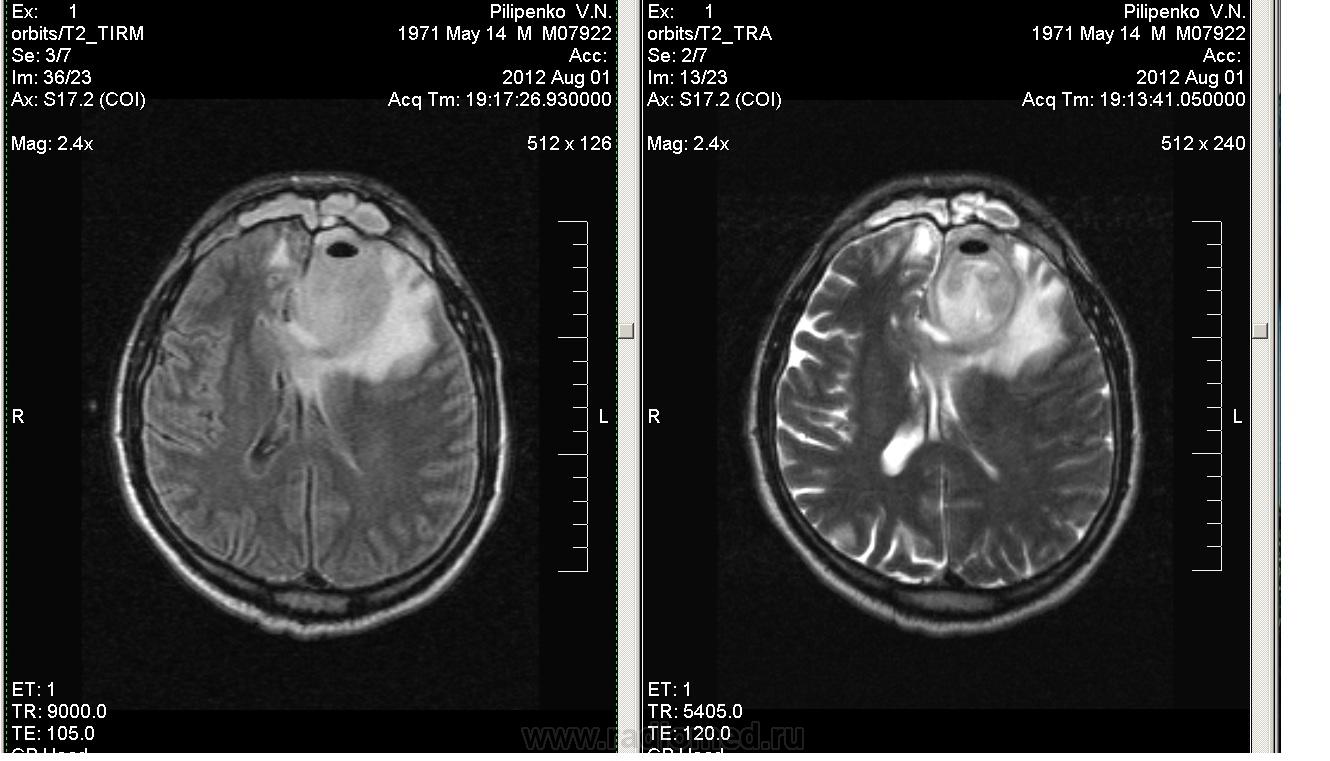

Мужчина средних лет. В анамнезе 3 года назад ЗЧМТ, обратились в частном порядке. Со слов жены, при госпитализации по поводу ЧМТ, был перелом лобной кости, головной мозг якобы без изменений. Медицинская документация не представлена. Настоящее исследование по поводу синусита, явившегося причиной 2-недельной госпитализации в ЛОР-центре (за 2,5 недели до посещения Нас).

Есть пленочка, на которую было нечто пролито, с трудом разглядели постэнцефаломаляцинные изменения в парасагиттальных отделах обеих лобных долей, да кисточку прозрачной перегородки (снимок через год после ЧМТ в сочетании с удивленным взглядом жены - "А нам сказали Норма"....????).

Мужчина заторможен, неадекватен и к состоянию не критичен, температура 38 в течении 2 недель. Пришел своими ногами.

У меня наверное извращенное чувство красоты, но не могу не поделиться.

Да, симпатичный абсцесс.И киста прозчной перегородки, смещение срединных структур+..интересно, кто как трактует расширенные субарахноидальные пространства-как проявление биполушарной кортикальной атрофии?У данного пациента в анамнезе ЧМТ, значит , все же гидроцефалия?Я иногда теряюсь-средний возраст у человека, иногда в ступор впадаю-наружной гидроцефалией назвать или кортикальной атрофией.Можно мне на "пальцах" разжевать?Спасибо заранее.